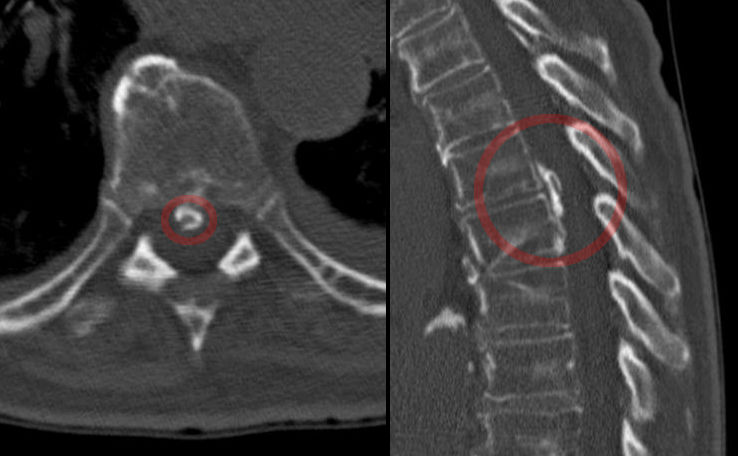

추간원판(디스크) 질환은 척추뼈 사이 원반 내부의 젤리 같은 물질인 수핵이 파열되어 발생하는 특이적 요통의 대표적인 원인이다.[16] 파열된 수핵이 신경 뿌리(신경근)를 압박하면 통증이나 관련 증상이 나타날 수 있다.[17] 증상은 압박받는 신경에 따라 한쪽 또는 양쪽 다리에 나타날 수 있으며, 주로 요추(허리뼈) 하부, 특히 4번과 5번 요추 사이(L4–L5) 또는 5번 요추와 천골(엉치뼈) 사이(L5–S1)에서 발생 빈도가 높다.[17] 과체중은 추간판에 가해지는 압력을 높여 질환 발생 위험을 증가시키며, 남성의 발생 확률이 여성보다 두 배 높다.[16][18] 2002년 연구에 따르면 야간 근무나 신체 활동 부족과 같은 생활 습관도 허리 추간원판 질환의 위험을 높일 수 있다.[19]

대부분의 급성 요통 환자에게 영상 검사는 필요하지 않다. 심각한 기저 질환을 시사하는 징후나 증상이 없다면, 영상 검사가 임상 결과를 개선하지 못하는 경우가 많다. 일반적으로 4~6주간의 보존적 치료 후에도 증상이 지속될 경우 영상 검사를 고려하는 것이 적절하다. 심각한 질환이 의심되는 경우에는 MRI가 일반적으로 가장 적합한 검사이다. MRI 촬영이 불가능하거나 금기인 경우, 컴퓨터 단층 촬영(CT)이 대안이 될 수 있다.[36] 급성 요통의 경우, 암, 척추 감염, 또는 심각하고 진행성인 신경학적 결손에 대한 주요 위험 요인이 있거나 임상적으로 의심될 때 MRI가 권장된다.[37] 아급성 또는 만성 요통 환자의 경우, 암, 강직성 척추염, 척추 압박 골절에 대한 경미한 위험 요인이 있거나, 심각한 외상 또는 증상이 있는 척추관 협착증이 있는 경우 MRI가 권장된다.[37]